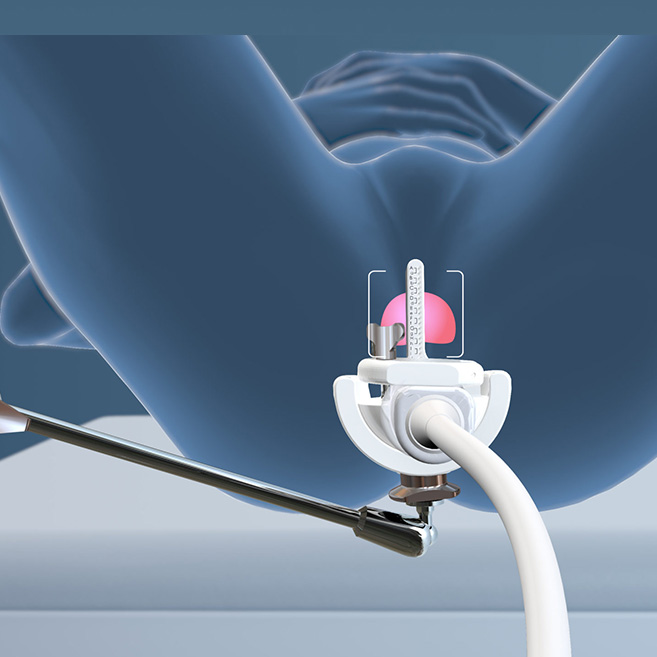

Transperineal

Procedures

KOELIS® offers a 3D side-fire ultrasound probe, probe holder and guides that improve visualization and during transperineal prostate biopsy.